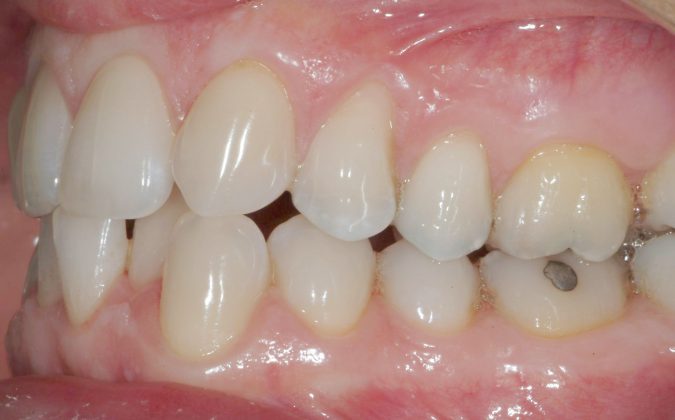

Una paziente di sesso femminile, 38 anni, già trattata ortodonticamente presso altra sede con apparecchiatura fissa a entrambe le arcate in età adolescenziale senza successiva applicazione di alcuna contenzione, si presenta alla nostra attenzione perché insoddisfatta dell’estetica del sorriso; richiede una valutazione per un trattamento ortodontico con apparecchiatura fissa linguale per la presenza di affollamento dentale a entrambe le arcate e difficoltà a mantenere una adeguata igiene orale; si riscontrano agenesia di entrambi gli incisivi laterali superiori (1.2 e 2.2) e del secondo premolare inferiore destro (4.5). Presentiamo la risoluzione del caso mediante trattamento ortodontico estrattivo a entrambe le arcate, eseguito con apparecchiatura linguale invisibile 2D e meccanica asimmetrica e seguito a medio termine da riabilitazione implanto-protesica e contenzione fissa.

Per formulare corretta diagnosi e piano di cura, lo studio del caso ha previsto la raccolta di documentazione completa standard, ovvero fotografie del viso e intraorali (Figure 1a-e), radiografia panoramica e teleradiografia del cranio in proiezione laterale (Figure 2a-b) per la relativa analisi cefalometrica e modelli di studio.

La valutazione clinica e gli esami effettuati confermano la presenza di agenesia degli incisivi laterali superiori (1.2 e 2.2) e del secondo premolare inferiore destro (4.5).

L’analisi ortodontica e la valutazione parodontale, con particolare riferimento alla posizione della radice del canino superiore destro (1.3), distoinclinata e trasposta alla radice del primo premolare (1.4) come evidente dalla radiografia panoramica e dalle immagini intraorali, ci hanno guidati nella programmazione di un trattamento estrattivo asimmetrico a entrambe le arcate.